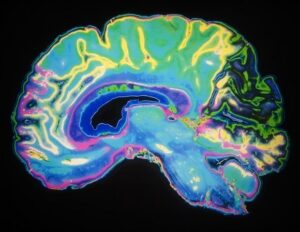

Για τις γυναίκες που είναι ασυμπτωματικές και έχουν πυκνούς μαστούς, το ACP προτείνει στους γιατρούς να εξετάσουν τη χρήση συμπληρωματικής ψηφιακής τομοσύνθεσης (DBT). Οι αποφάσεις αυτές θα πρέπει να λαμβάνουν υπόψη τα πιθανά οφέλη και τις βλάβες, την έκθεση σε ακτινοβολία, τη διαθεσιμότητα, τις προτιμήσεις των ασθενών και το κόστος. Ωστόσο, η χρήση συμπληρωματικής μαγνητικής τομογραφίας (MRI) ή υπερήχων για την εξέταση αυτή δεν συνιστάται.